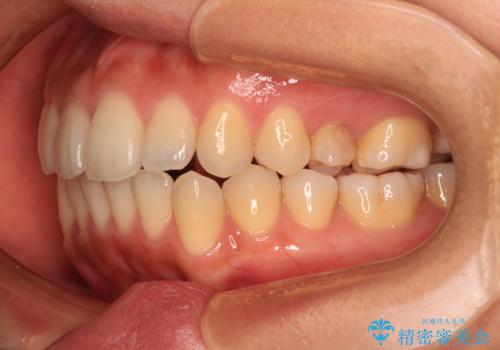

- 前歯のデコボコと咬み合わせを気にして来院された患者様です。

左上奥歯には乳歯が残存しており、後続永久歯は舌側に転位していました。

また、舌の突出癖の影響で上下前歯が接触していないオープンバイトとなっており、奥歯に負担のかかる咬み合わせとなっていました。

舌のトレーニングをしっかりと行ってくださり、前歯部のオープンバイトは大幅に改善されました。

もう少しでよりタイトに前歯が接触できそうでしたが、患者様がもう十分とのことで治療を終了しました。